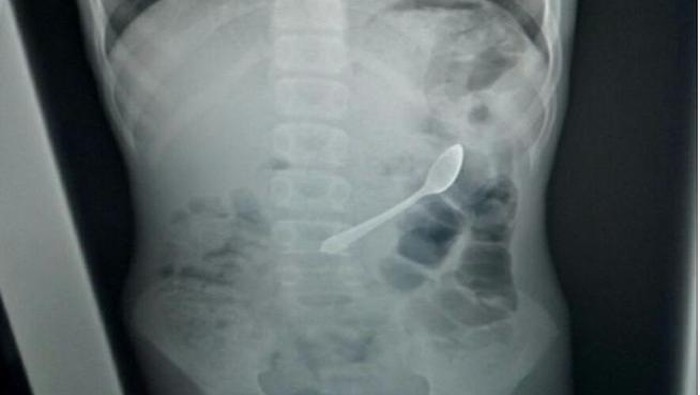

Dokter lalu melakukan rontgen pada bocah tersebut, dan benar saja tampak sebuah sendok sepanjang 11 cm tersangkut di dalam di usus.

Penampakan sendok yang berhasil dikeluarkan. Foto: International Medical Case Reports Journal |